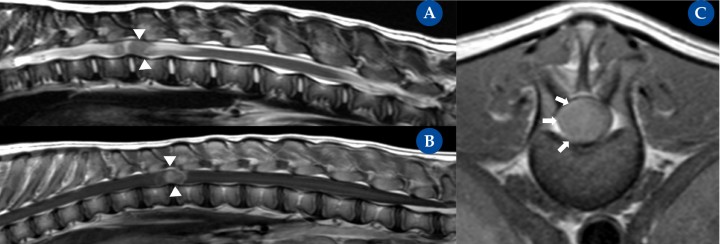

Figura 5

Tumor intramedular (nefroblastoma). Resonancia magnética: plano sagital ponderada en T2 (A), ponderada en T1 post contraste (B) y transversal ponderada en T1 post contraste (C) en un bulldog americano, de 5 meses de edad, hembra entera, con una historia crónica progresiva, de 6 semanas de evolución, de ataxia generalizada propioceptiva en ambos miembros pélvicos y paraparesia ambulatoria severa. La resonancia magnética mostró una masa intramedular (aunque inicialmente no se pudo descartar un componente intradural) a nivel de T12-T13 con realce focal y homogéneo tras la administración de contraste. La masa ocupa la casi totalidad del área de la médula espinal. En la secuencia de T2 se aprecian cambios intramedulares craneal y caudal a la masa intramedular compatible con edema medular. La posterior necropsia de la paciente confirmó la existencia de un nefroblastoma intramedular.